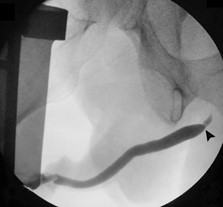

Retrograde urethrogram was performed by introducing contrast through a catheter-tip syringe into the urethra. Fluoroscopic images showed a proximal short and narrow bulbar urethral stricture (Figure 1), which explained patient's complaints of incomplete bladder emptying, difficulty urinating, slow stream, and frequency. Accordingly, cystoscopy with urethral balloon dilation was accomplished.